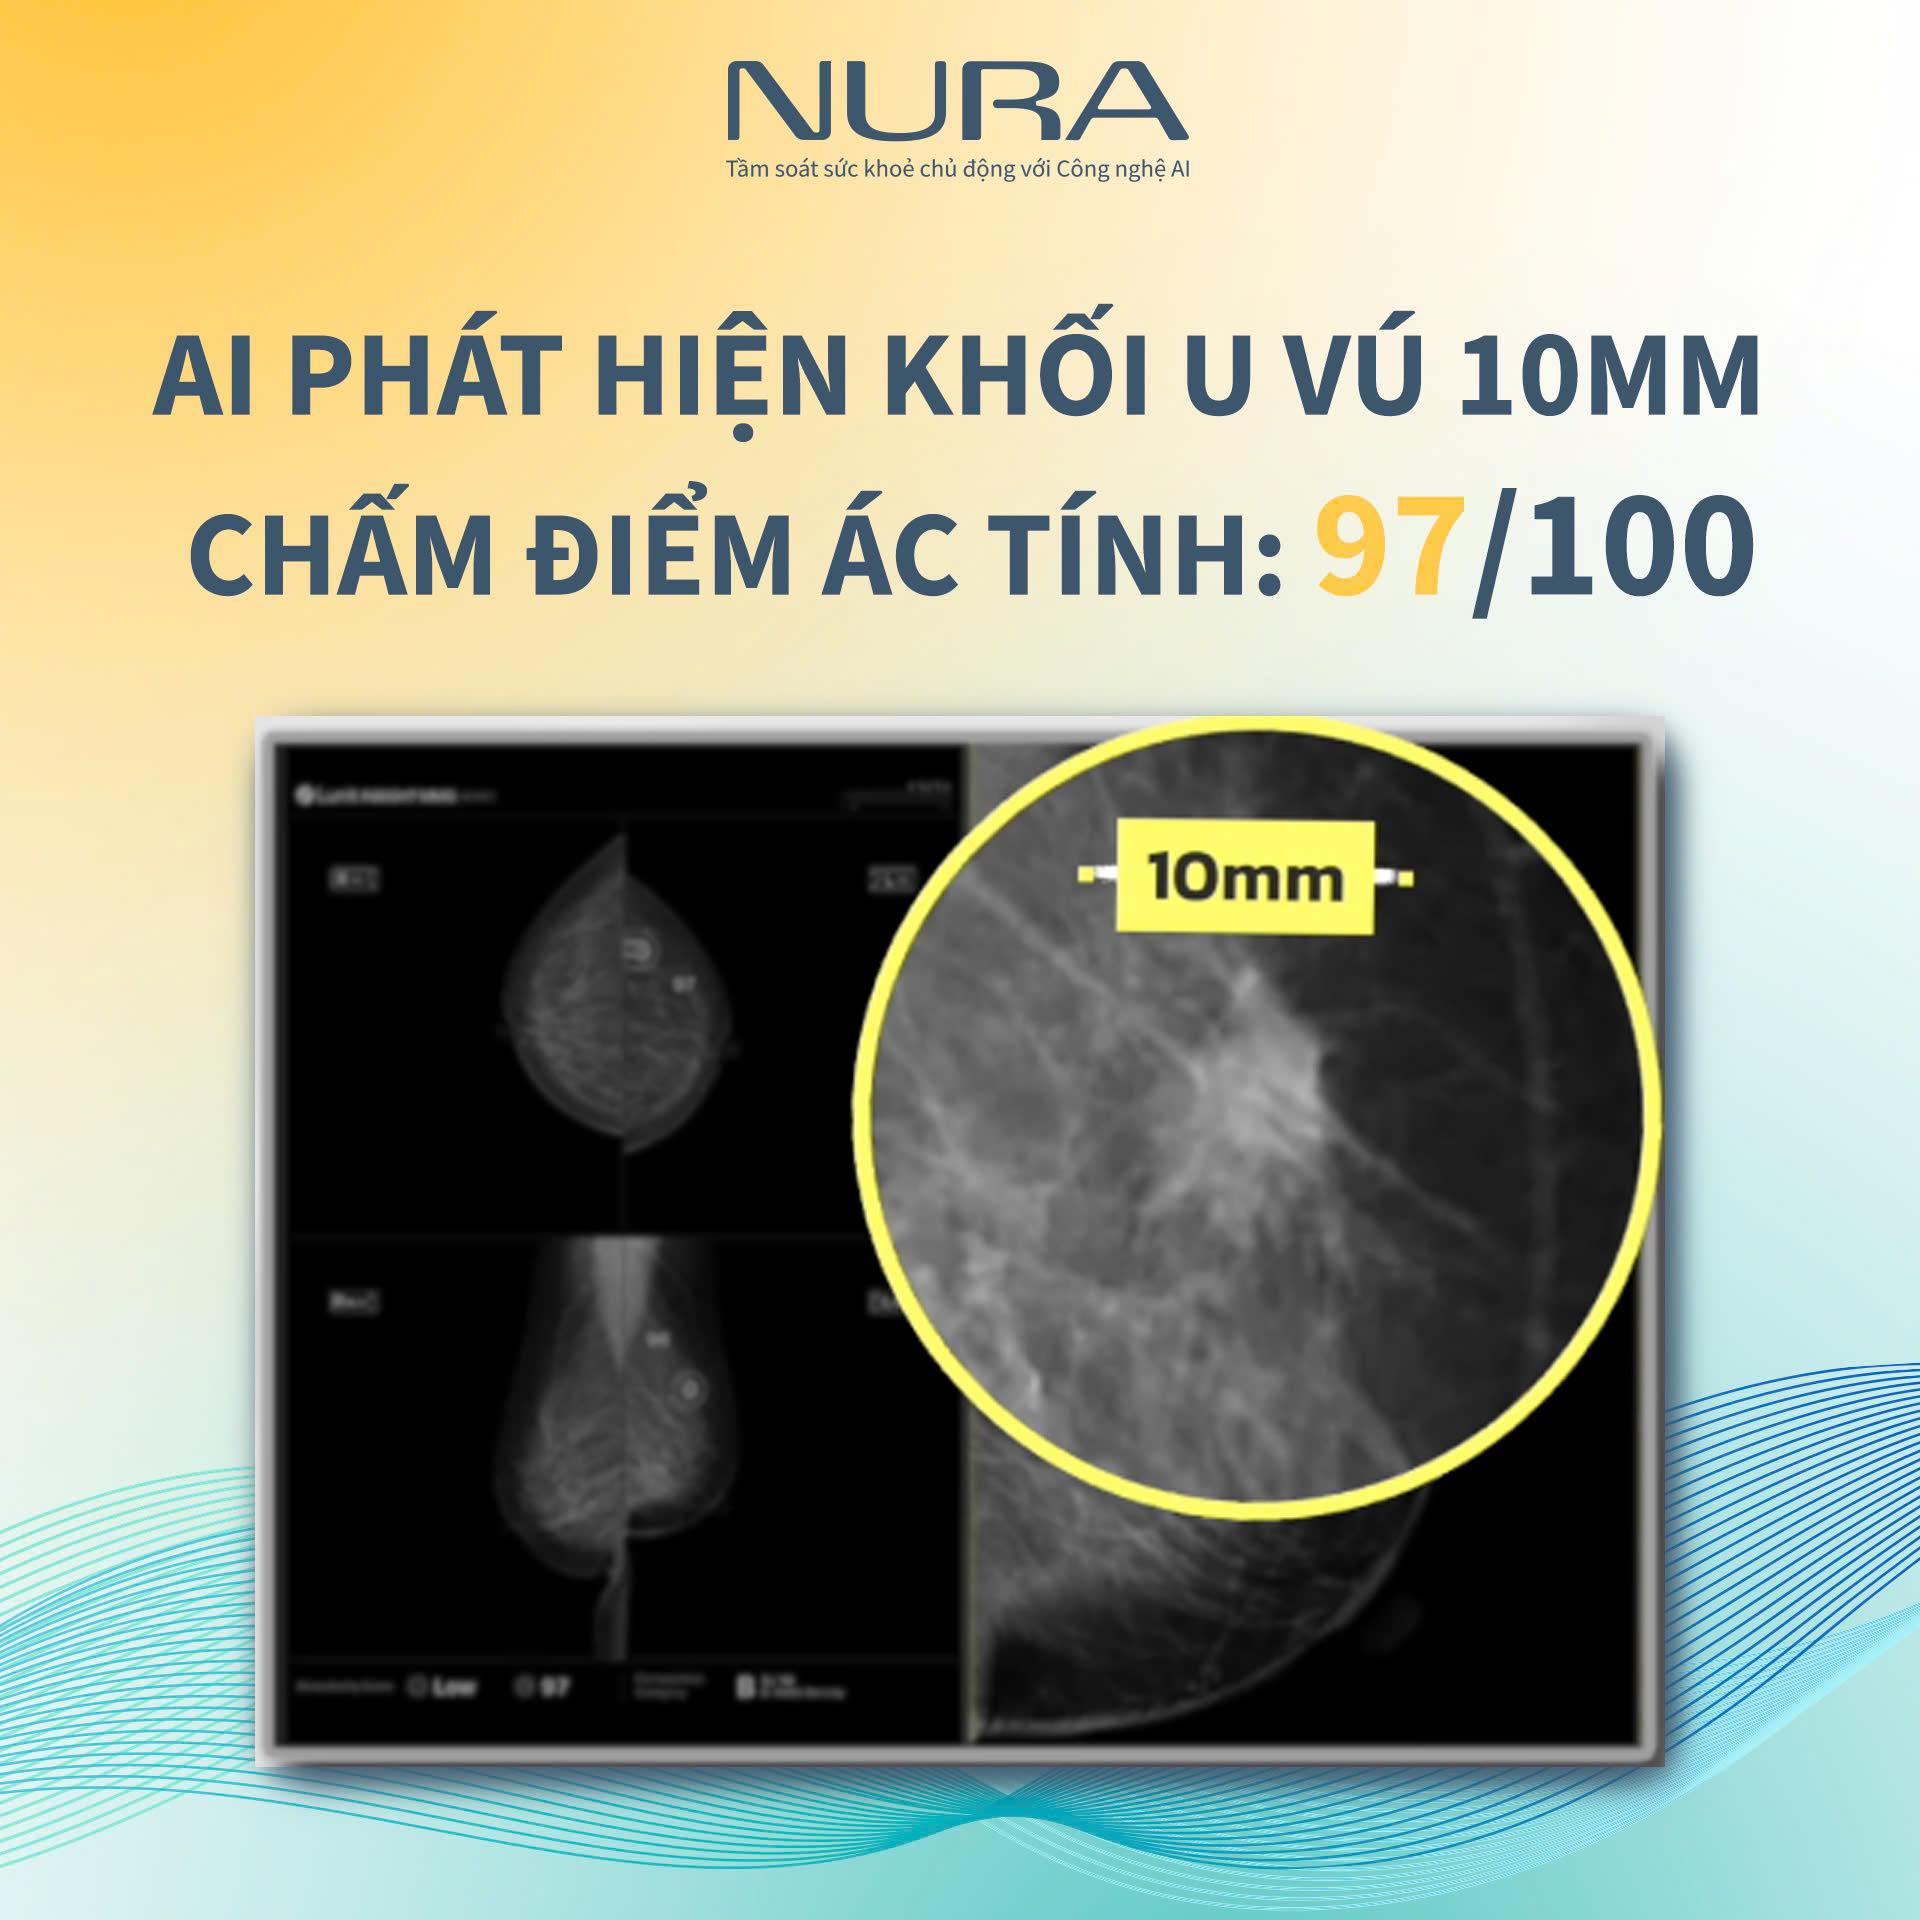

Phát hiện khối u vú 10mm bị bỏ sót cho bệnh nhân có siêu âm định kỳ hàng năm

Một trường hợp bệnh nhân nữ đã thực hiện siêu âm tuyến vú đều đặn mỗi năm trong thời gian dài tới tầm soát 14 bệnh ung thư và 22 bệnh lối sống tại Nura. Kết quả chụp nhũ ảnh (Mammography) được trí tuệ nhân tạo AI phát hiện một khối u kích thước 10mm ở ngực trái.

Nhìn trên kết quả chụp nhũ ảnh, bằng mắt thuờng rất dễ bỏ sót khối u này bởi sự khác biệt giữa mô bất thường và mô lành tính hầu như không đáng kể. Điều này cho thấy việc thực hiện tầm soát định kỳ không có nghĩa là bạn có thể phát hiện bệnh sớm. Tầm soát không chỉ cần “đúng lịch”, định kỳ, mà còn cần “đúng phương pháp” đi kèm với thiết bị hiện đại.